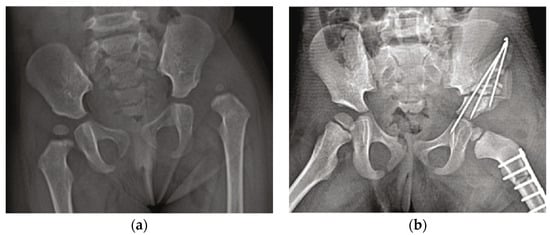

- Yu, J.; Shi, Q. Efficacy Evaluation of 3D Navigational Template for Salter Osteotomy of DDH in Children. BioMed Res. Int. 2021, 2021, 8832617. [Google Scholar] [CrossRef] [PubMed]